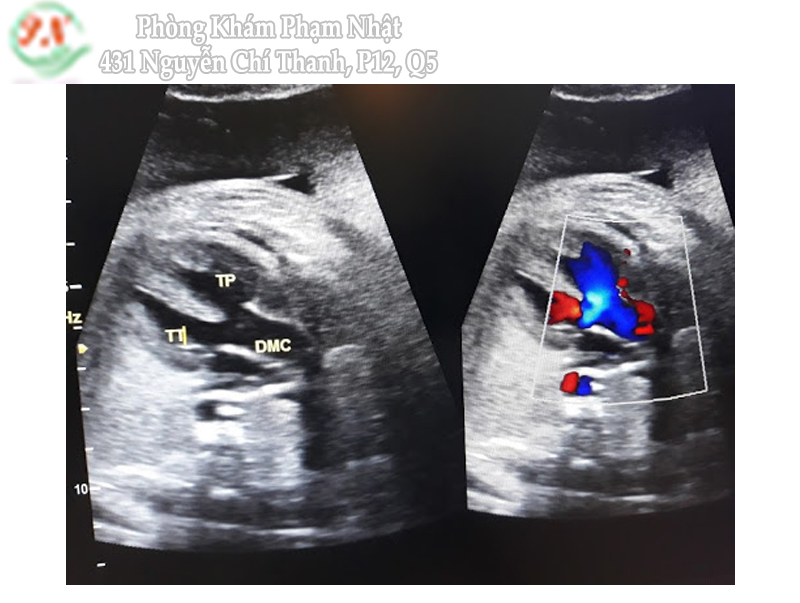

Sóng a đảo ngược trong ống tĩnh mạch

Ống tĩnh mạch (ductus venosus) là một mạch máu nhỏ nối từ tĩnh mạch rốn đến tĩnh mạch chủ dưới.

Khi có xuất hiện sóng a đảo ngược trong ống tĩnh mạch sẽ đi kèm với tăng nguy cơ thai có bất thường NST hay bất thường tim.

Sóng a đảo ngược của ống tĩnh mạch xuất hiện gặp trong những trường hợp: 65% trisomy 21; 55% trisomy 18; 55% trisomy 13 và chỉ 3% gặp ở những thai không bất thường số lượng NST.

Việc khảo sát sóng a đảo ngược của ống tĩnh mạch thai nhi khi kết hợp với đo NT và sinh hóa máu mẹ sẽ làm cải thiện tỷ lệ phát hiện 95%. Từ đó làm giảm tỷ lệ dương tính giả xuống còn 2.5%.

Dòng phụt ngược qua van 3 lá

Bình thường tim thai nhi không có dòng phụt ngược qua van 3 lá. Nếu xuất hiện dòng phụt ngược qua van 3 lá với thời gian > ½ thì tâm thất thu và vận tốc dòng phụt ngược > 60cm/s được xem là bất thường.

Dòng phụt ngược qua van 3 lá gặp trong những trường hợp: 55% trisomy 21; 30% trisomy 18; 30% triosmy 13 và 1% gặp ở những thai có số lượng NST bình thường.